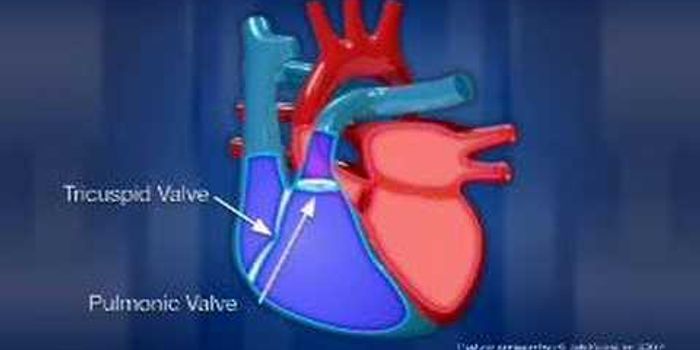

DEC 16, 2017VideosThe blood is filtered by the kidneys, which remove the toxins and wastes and then send them along to the bladder along w ...